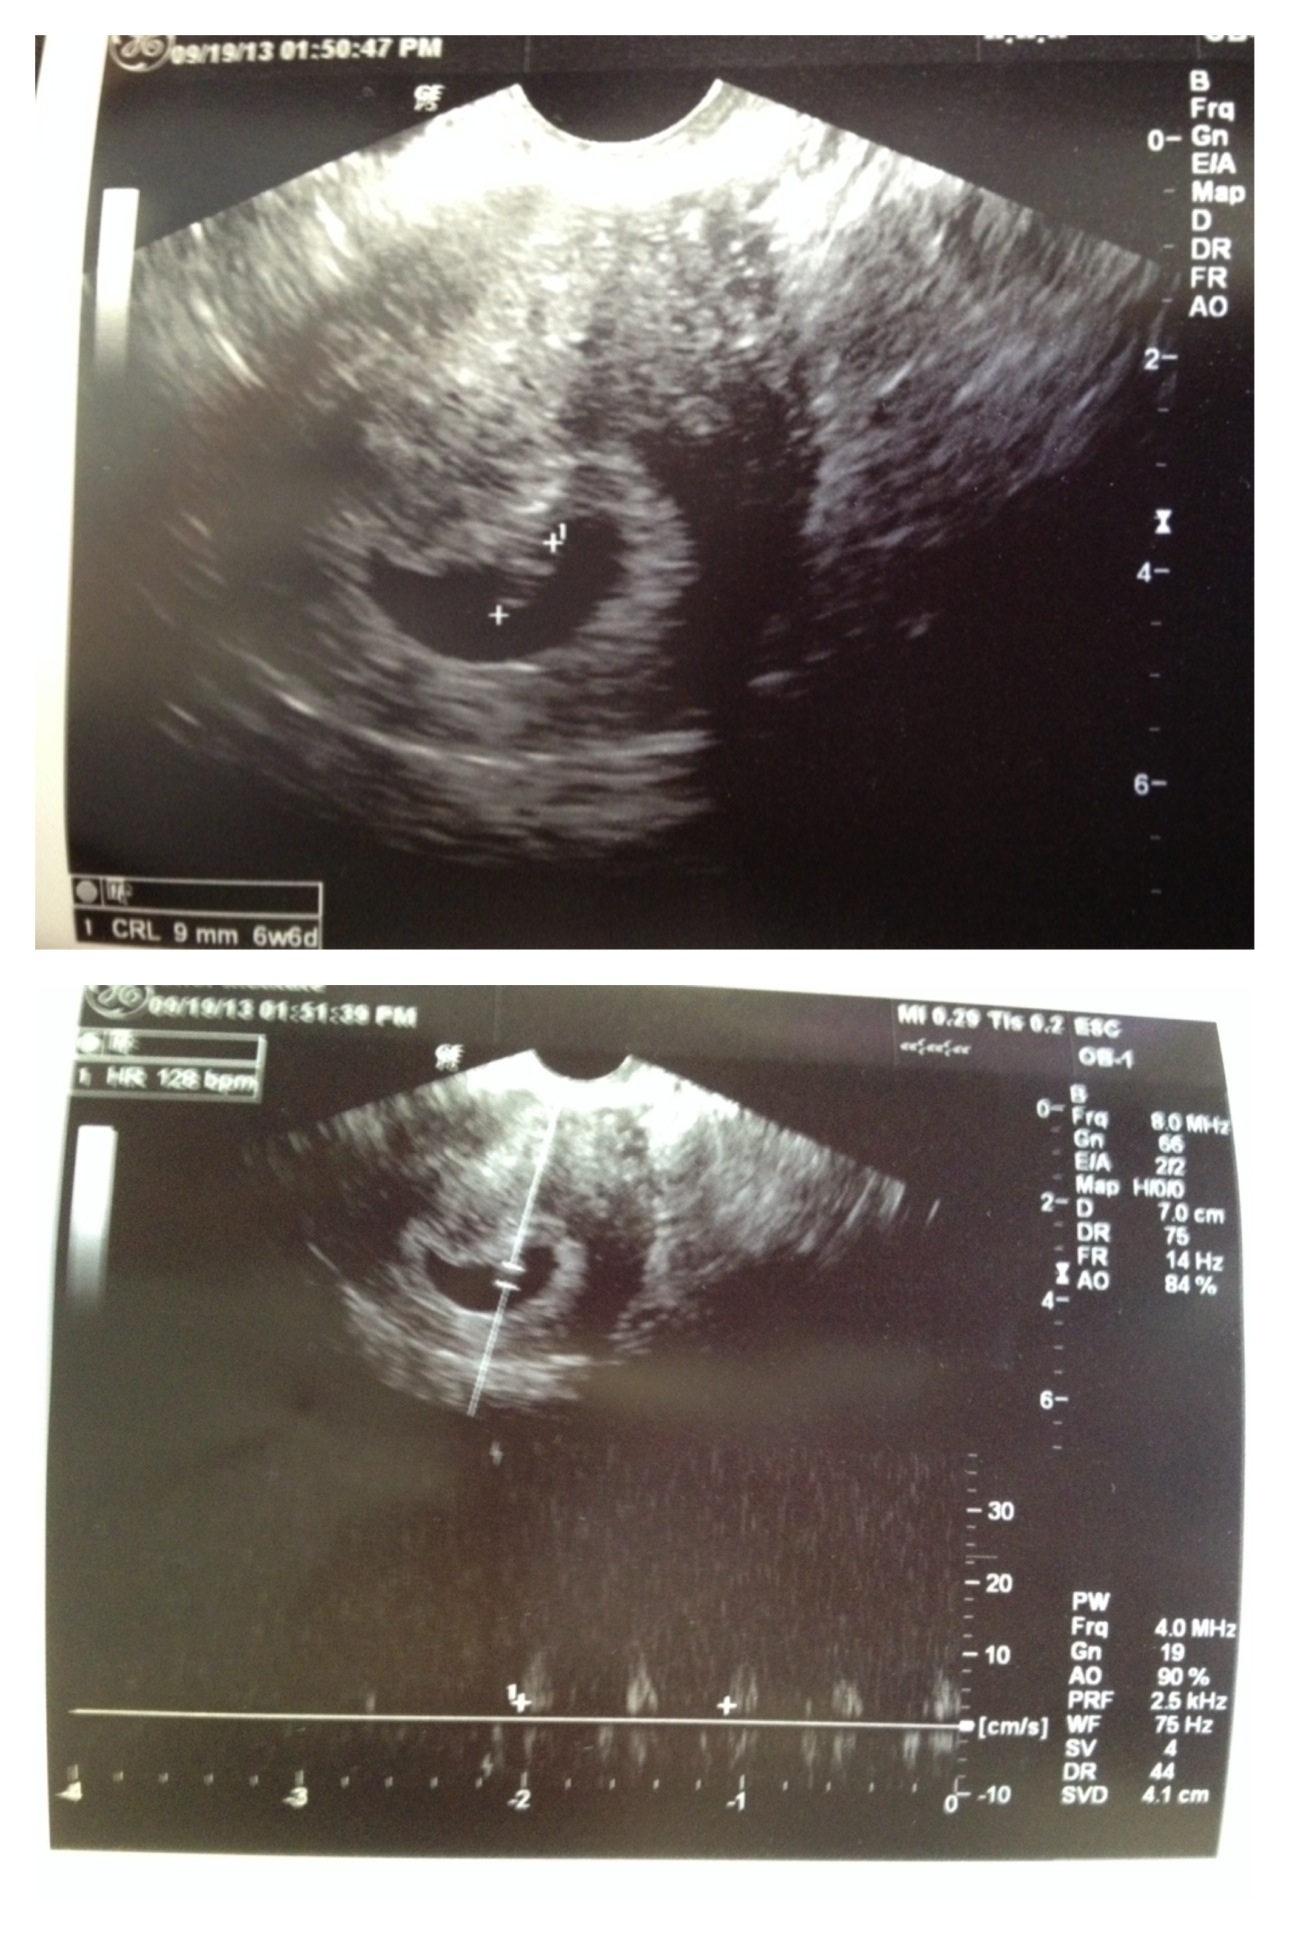

I have a perfect bean inside a perfect sac with a perfect hr of 128 bpm. Measuring 6w6d on the dot. Holy shit I am for real KU! I go back on 10/4 for another ultrasound and my last round of intralipids, and then I will graduate from the RE! Squeeeee!

U/S 9/19/13- HR is 128!  U/S #2 10/4/13- HR is 174!